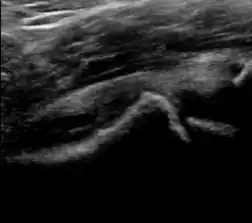

During childhood, ultrasound is a quick method to assess hip pain and quite often may be used to avoid use of irradiating techniques, such as radiography or CT. Ultrasound allows evaluation of joint effusion, synovial thickening and neovascularity, the bone/cartilage contour, and the femoral head-neck alignment. Although sonography is extremely sensitive in detecting increased synovial fluid, it is nonspecific and cannot be used with accuracy to determine the type of fluid. Transient synovitis of the hip, despite being the most frequent cause of pain in children between 3 and 10 years, remains a diagnosis of exclusion. It usually shows anechoic fluid, but echogenic fluid can also be found. The effusion is considered pathologic when it is measured at >2 mm in thickness. The differential diagnosis is wide, including osteomyelitis, septic arthritis, primary or metastatic lesions, LCPD, and SCFE. Discrimination from septic arthritis is challenging, often requiring joint aspiration. In septic arthritis, US is able to demonstrate a hip joint effusion, synovial thickening, and cartilage damage, although the appearances are nonspecific.[1]

A step between the head and the physis can be detected in children with SCFE, while abnormalities in the femoral head contour may suggest the presence of LCPD. In both cases, radiographs are mandatory to confirm diagnosis and severity (Figure 12).[1]

Figure 12:

-

Normal ultrasound appearance of the femoral head-neck junction. -

Joint effusion in transient synovitis of the hip. -

Flattening of the femoral head in a patient with Perthes disease. -

Step in the femoral head-neck junction in a patient with SCFE.